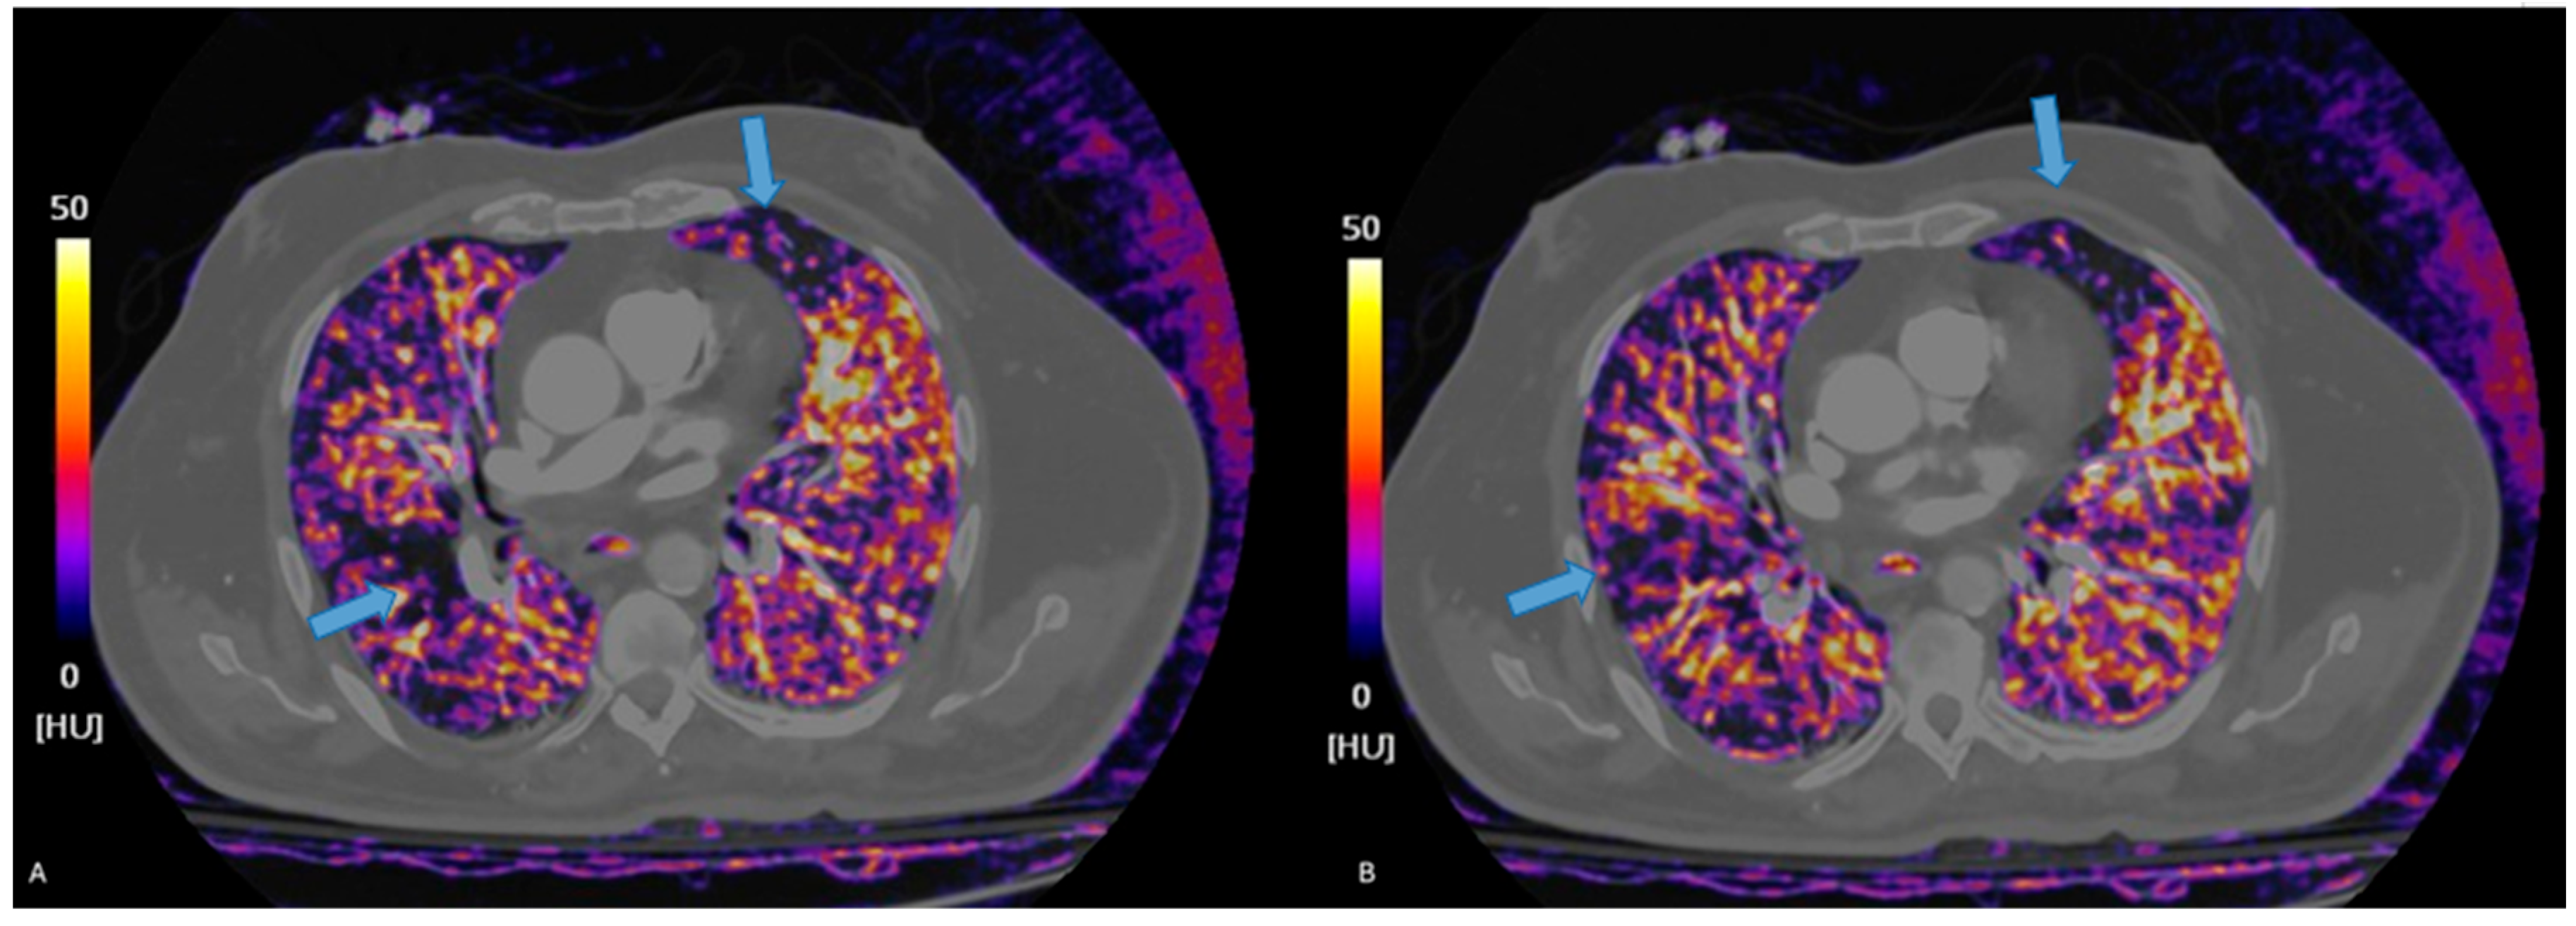

3.3. Photon-Counting CT

3.3.1. Principles of Photon Counting

3.3.2. Diagnostic Accuracy of of Photon Counting-CTPA